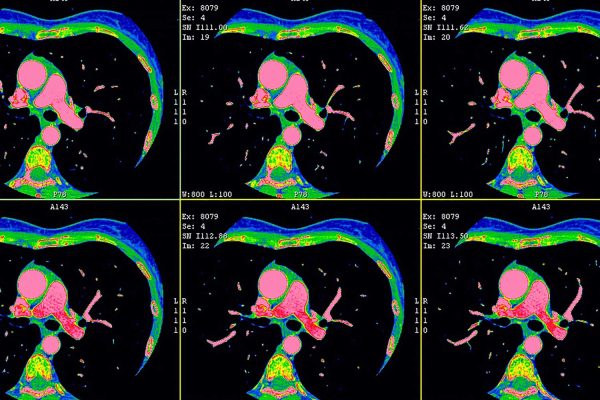

What Is a CT Scan? How It Works, What It Shows, and What to Expect

A CT scan is a powerful medical imaging test that helps doctors see detailed pictures of the inside of your body. At IPMC in Northeast Philadelphia, we offer advanced CT imaging in a comfortable outpatient setting so you can get answers quickly without the stress of a hospital visit.